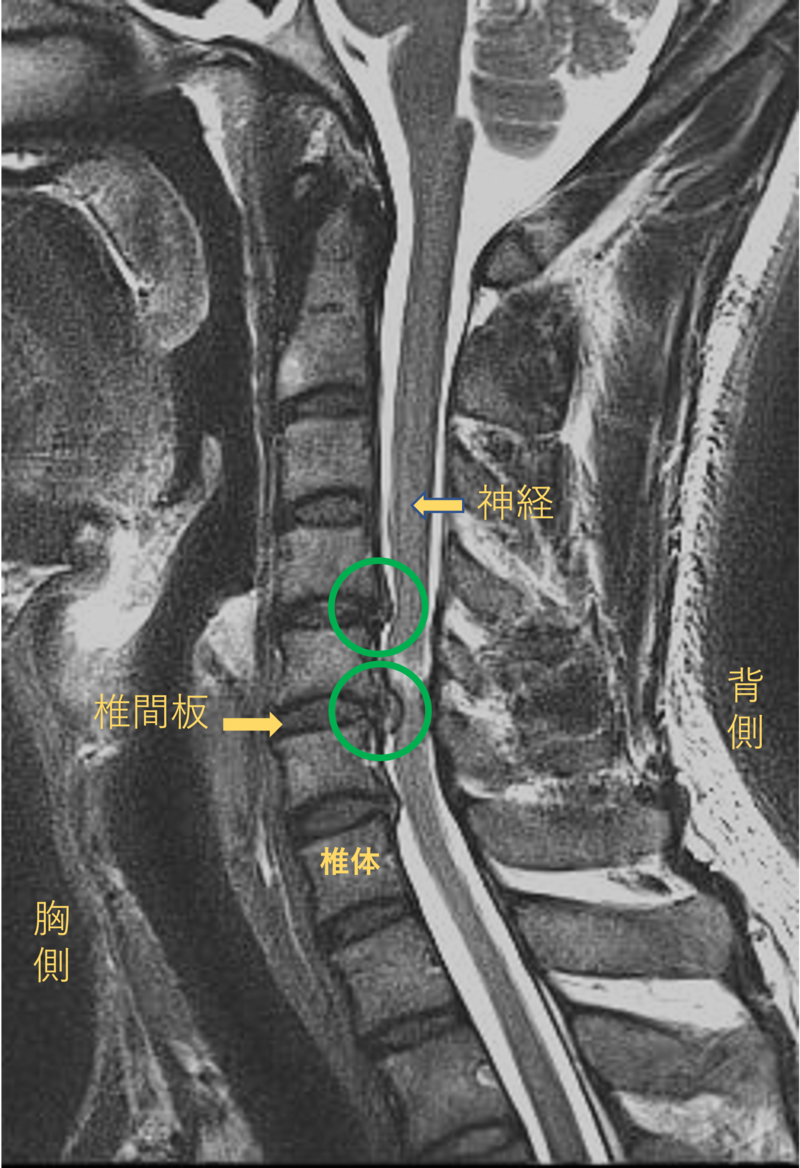

首を横から見たMRI画像です。

頚椎という骨と骨の間に椎間板と呼ばれるクッションがあります。

このクッションの中身が飛び出す状態が椎間板ヘルニアと呼ばれます。

このMRI画像では、椎間板が背中側に飛び出して神経が圧迫されることがしびれの原因となっておりました。